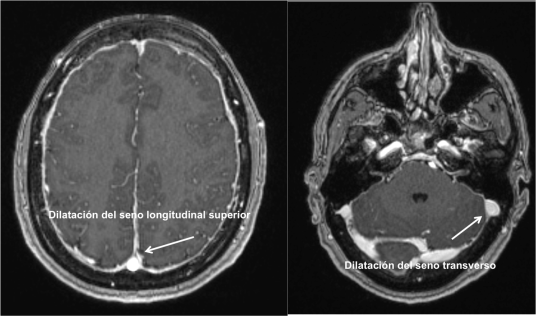

Según la hipótesis de Monro-Kellie cualquier variación del volumen de LCR debe ser compensado dado la naturaleza no compresible del cráneo. Como consecuencia, la pérdida de volumen de LCR se compensa con un aumento del volumen intracraneal y se produce una congestión venosa. Esta congestión venosa es visible en la Resonancia Cerebral y da lugar a una hipercaptación difusa meníngea.

En la Imagen 4 y 5 podemos ver el aspecto congestivo y redondeado de los senos venosos longitudinal y transverso.